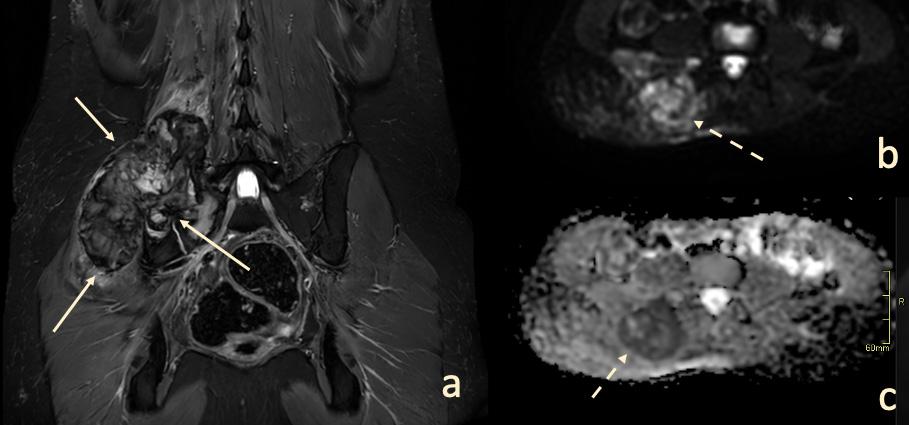

DIFFUSIONSVIKTAD MAGNETRESONANSAVBILDNING

Diffusionsviktad avbildning (DWI) gör det möjligt att bedöma diffusionen av vattenmolekyler i vävnader, vilket relaterar till bland annat celltätheten i den undersökta vävnaden. Den morfologiska grunden är det faktum att vattenmolekylernas diffusionsrörelse hindras av membran och makromolekyler i vävnad, vilket kan förväntas ske till högre grad i maligna förändringar som i sarkom som vanligtvis har en ökad celltäthet, jämfört med oförändrade vävnader och godartade förändringar.2 Nyligen publicerade studier har, i linje med detta, visat att DWI har potential att göra det lättare att skilja mellan godartade och maligna förändringar i det muskuloskeletala systemet jämfört med konventionella MR-sekvenser7,8

Användningen av DWI (Bild 1) skulle kunna minska behovet av kontrastmedel vid kontrollundersökningar efter tumöroperationer eftersom dagens diagnostik med konventionella MR-sekvenser till stor del bygger på bedömning av kontrastmedelsuppladdning i suspekta vävnader. DWI har dock sina begränsningar, bland annat på grund av magnetfältets inhomogenitet i ojämna områden av vår kropp (till exempel området kring axelleden där det finns en disproportion mellan dimensionerna av nacken och axlarna samt närvaron av rörliga lungor, stora kärl etc.) vilket leder till tex bildförvrängningar och artefakter. Diffusion är en känslig metod, men dess användning inom rörelseapparatens system är för närvarande inte stor, eftersom det saknas studier på större material.

Diffusion tensor imaging (DTI), (Bild 2) är en variant av DWI som syftar till att avbilda den riktningsberoende signalen hos vattenmolekylernas diffusion i vävnaden. Inom rörelseapparaten kan DTI används för att avbilda diffusionen längs muskelfibrer9 för att bedöma skador på muskler som inte är synliga i konventionella sekvenser, vilket kan vara av betydelse för att upptäcka mindre, interna muskelskador hos idrottare.10,11 I utredningen av tumörer i, eller i anslutning till, nerver kan DTI används för att bedöma huruvida diffusionen längs med nerven är påverkad och därmed ge information om nervens integritet (Bild 2). Detta är relevant i differentialdiagnosen tex mellan nervtumörer och nervskidetumörer12 eller mellan lokalt växande och infiltrativa tumörer.13,14

Bild 1. En 20-årig patient med en palpabel tumor i området kring höger höft (a - pilar). MRT visade en förändring med begränsad diffusion (b och c - streckad pil). Biopsi visade osteosarkom. a – Koronalt snitt, T2 Short Tau Inversion Recovery (STIR), b - Diffusionsviktad bild (b 800), c - Apparent diffusion coefficient.